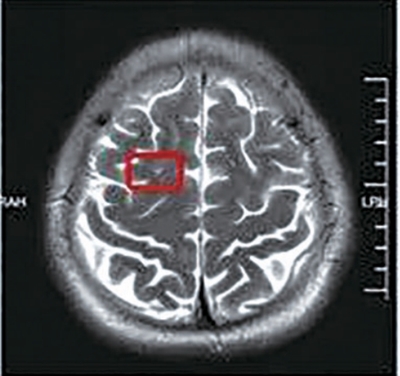

2025年8月20日   2026年3月6日   经过半年治疗,患者颅内病灶水肿逐渐吸收缩小。

经过系统性、针对性的规范治疗后,患者颅内病灶水肿逐渐吸收,出现缩小趋势。近日小王和妻子来杭州进行半年复查:颅内病灶较半年前明显缩小,身体抽搐症状消失。